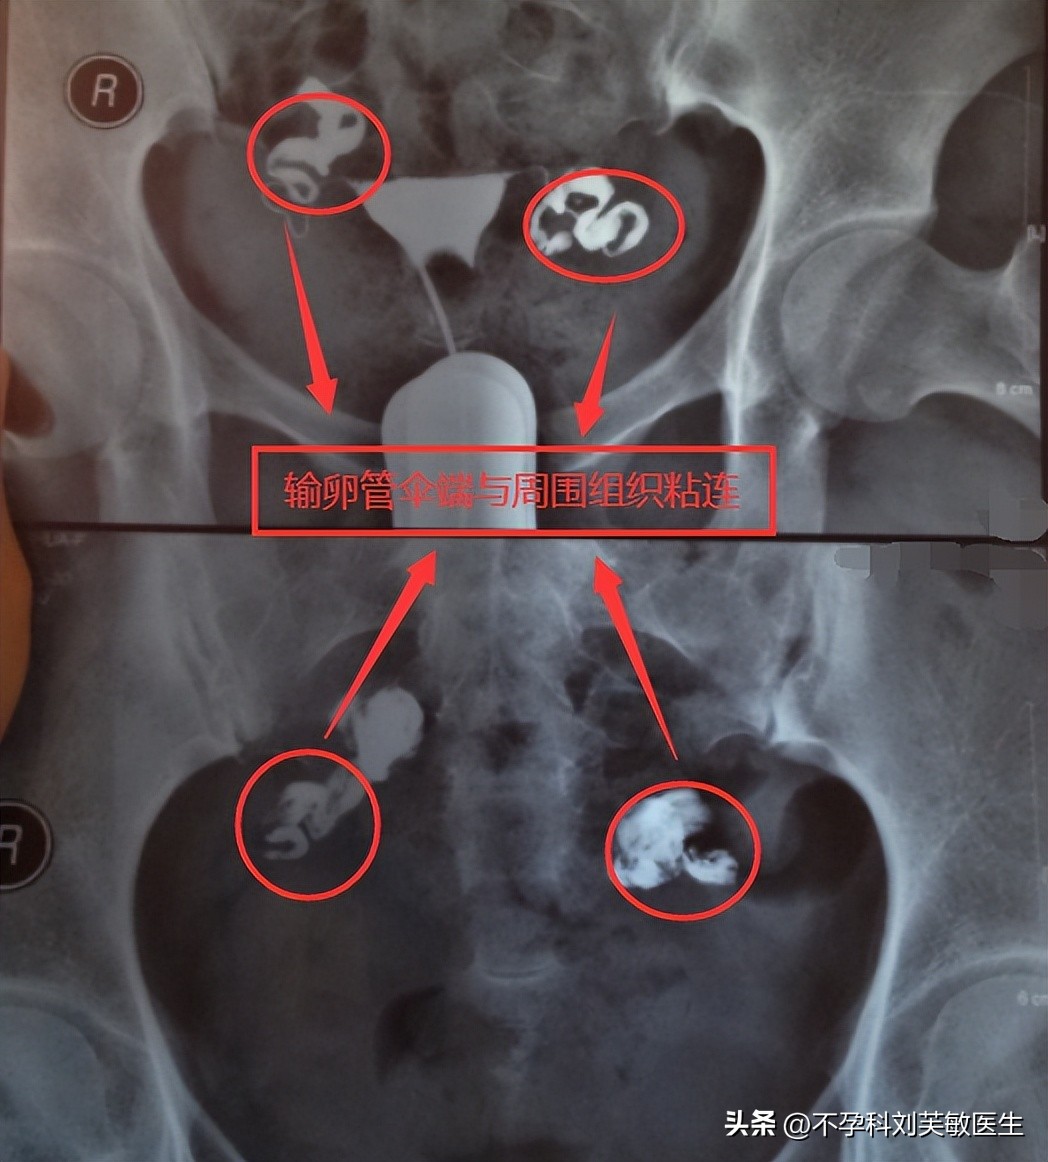

3.输卵管与周围组织粘连

造影剂自流入粘连间隙呈花蕾状,提示输卵管伞端与周围组织有粘连。或造影剂从输卵管流出后,积聚于输卵管周围呈囊状而不弥散。